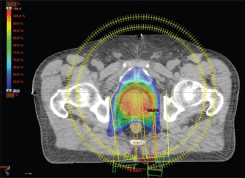

IMRT/IMAT techniques make it possible to deliver different levels of dose to different parts of the tumour (for instance, a hypoxic area of the tumour, identified by means of functional imaging, may receive a boost dose). Approaches using a simultaneous integrated boost (SIB) and the delivery of dose-escalated conventionally fractionated or hypo-fractionated RT using IMRT techniques are now being investigated as an alternative to conventional RT for different anatomical sites: breast [49, 50], head and neck [51, 52] prostate [53, 54]. Examples, using tomotherapy, of SIBs delivered to the breast tumour bed and to the dominant intra-prostatic lesions (DILs) are shown in Figures 1 and 2.

Figure 1. Axial view of a treatment plan for whole breast irradiation with SIB delivered with TomoTherapy. The colour green corresponds to 95% of the prescribed dose to the breast, and the colour red to 95% of the boost dose.

Figure 2. Axial view of a volumetric arc therapy (VMAT) treatment plan for prostate cancer delivered with RapidArc, with SIB to DILs.